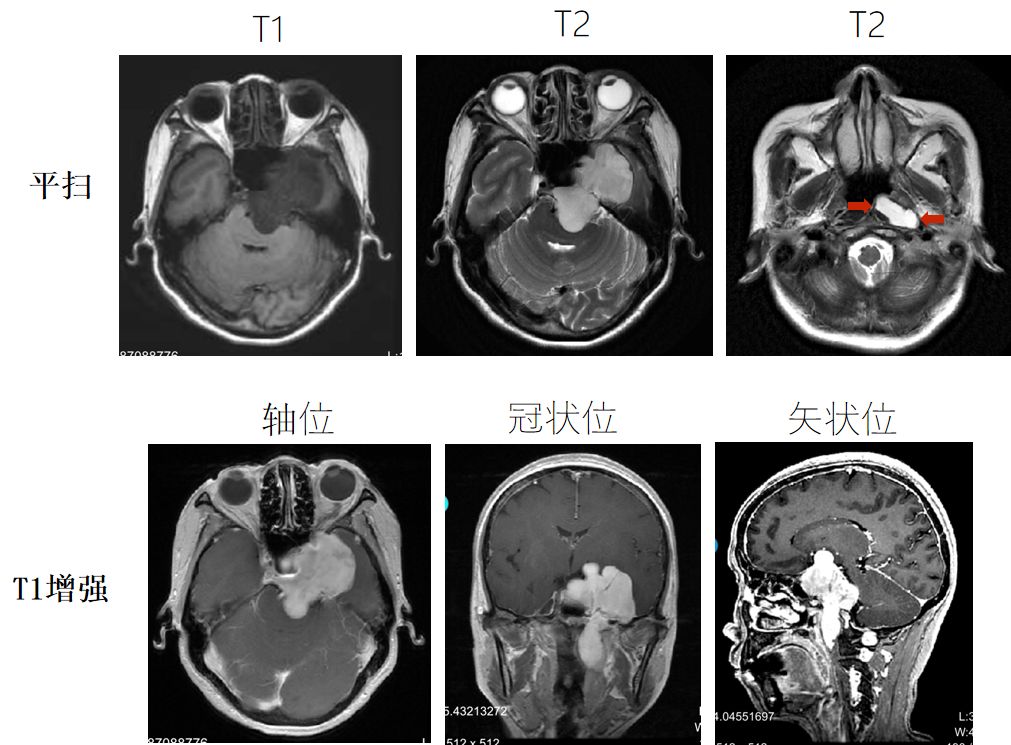

4. MRI:左侧中颅窝、海绵窦、鞍区、咽后间隙稍低密度肿块,大小约78x52x41 mm,T1WI低信号,T2WI高信号,DWI稍低信号,增强扫描明显强化。垂体及左颞叶受压移位。考虑三叉神经鞘瘤。

5. MRA:左侧ICA海绵窦段受压向前移位,部分被肿物包绕,未见充盈缺损,基底动脉受压向右移位。

术前MRI

中年女性,慢性病程;

三叉神经分布区域感觉及痛觉异常起病;

MRI:T1低信号,T2高信号,DWI稍低信号,强化明显;

病变位于三叉神经分布范围:以Meckel氏腔为中心向鞍上、海绵窦、中颅窝、后颅窝及颞下窝方向生长;

诊断为:左侧海绵窦区、中后颅窝及颞下窝巨大占位,三叉神经鞘瘤;

鉴别诊断:脑膜瘤、海绵窦海绵状血管瘤、胆脂瘤。